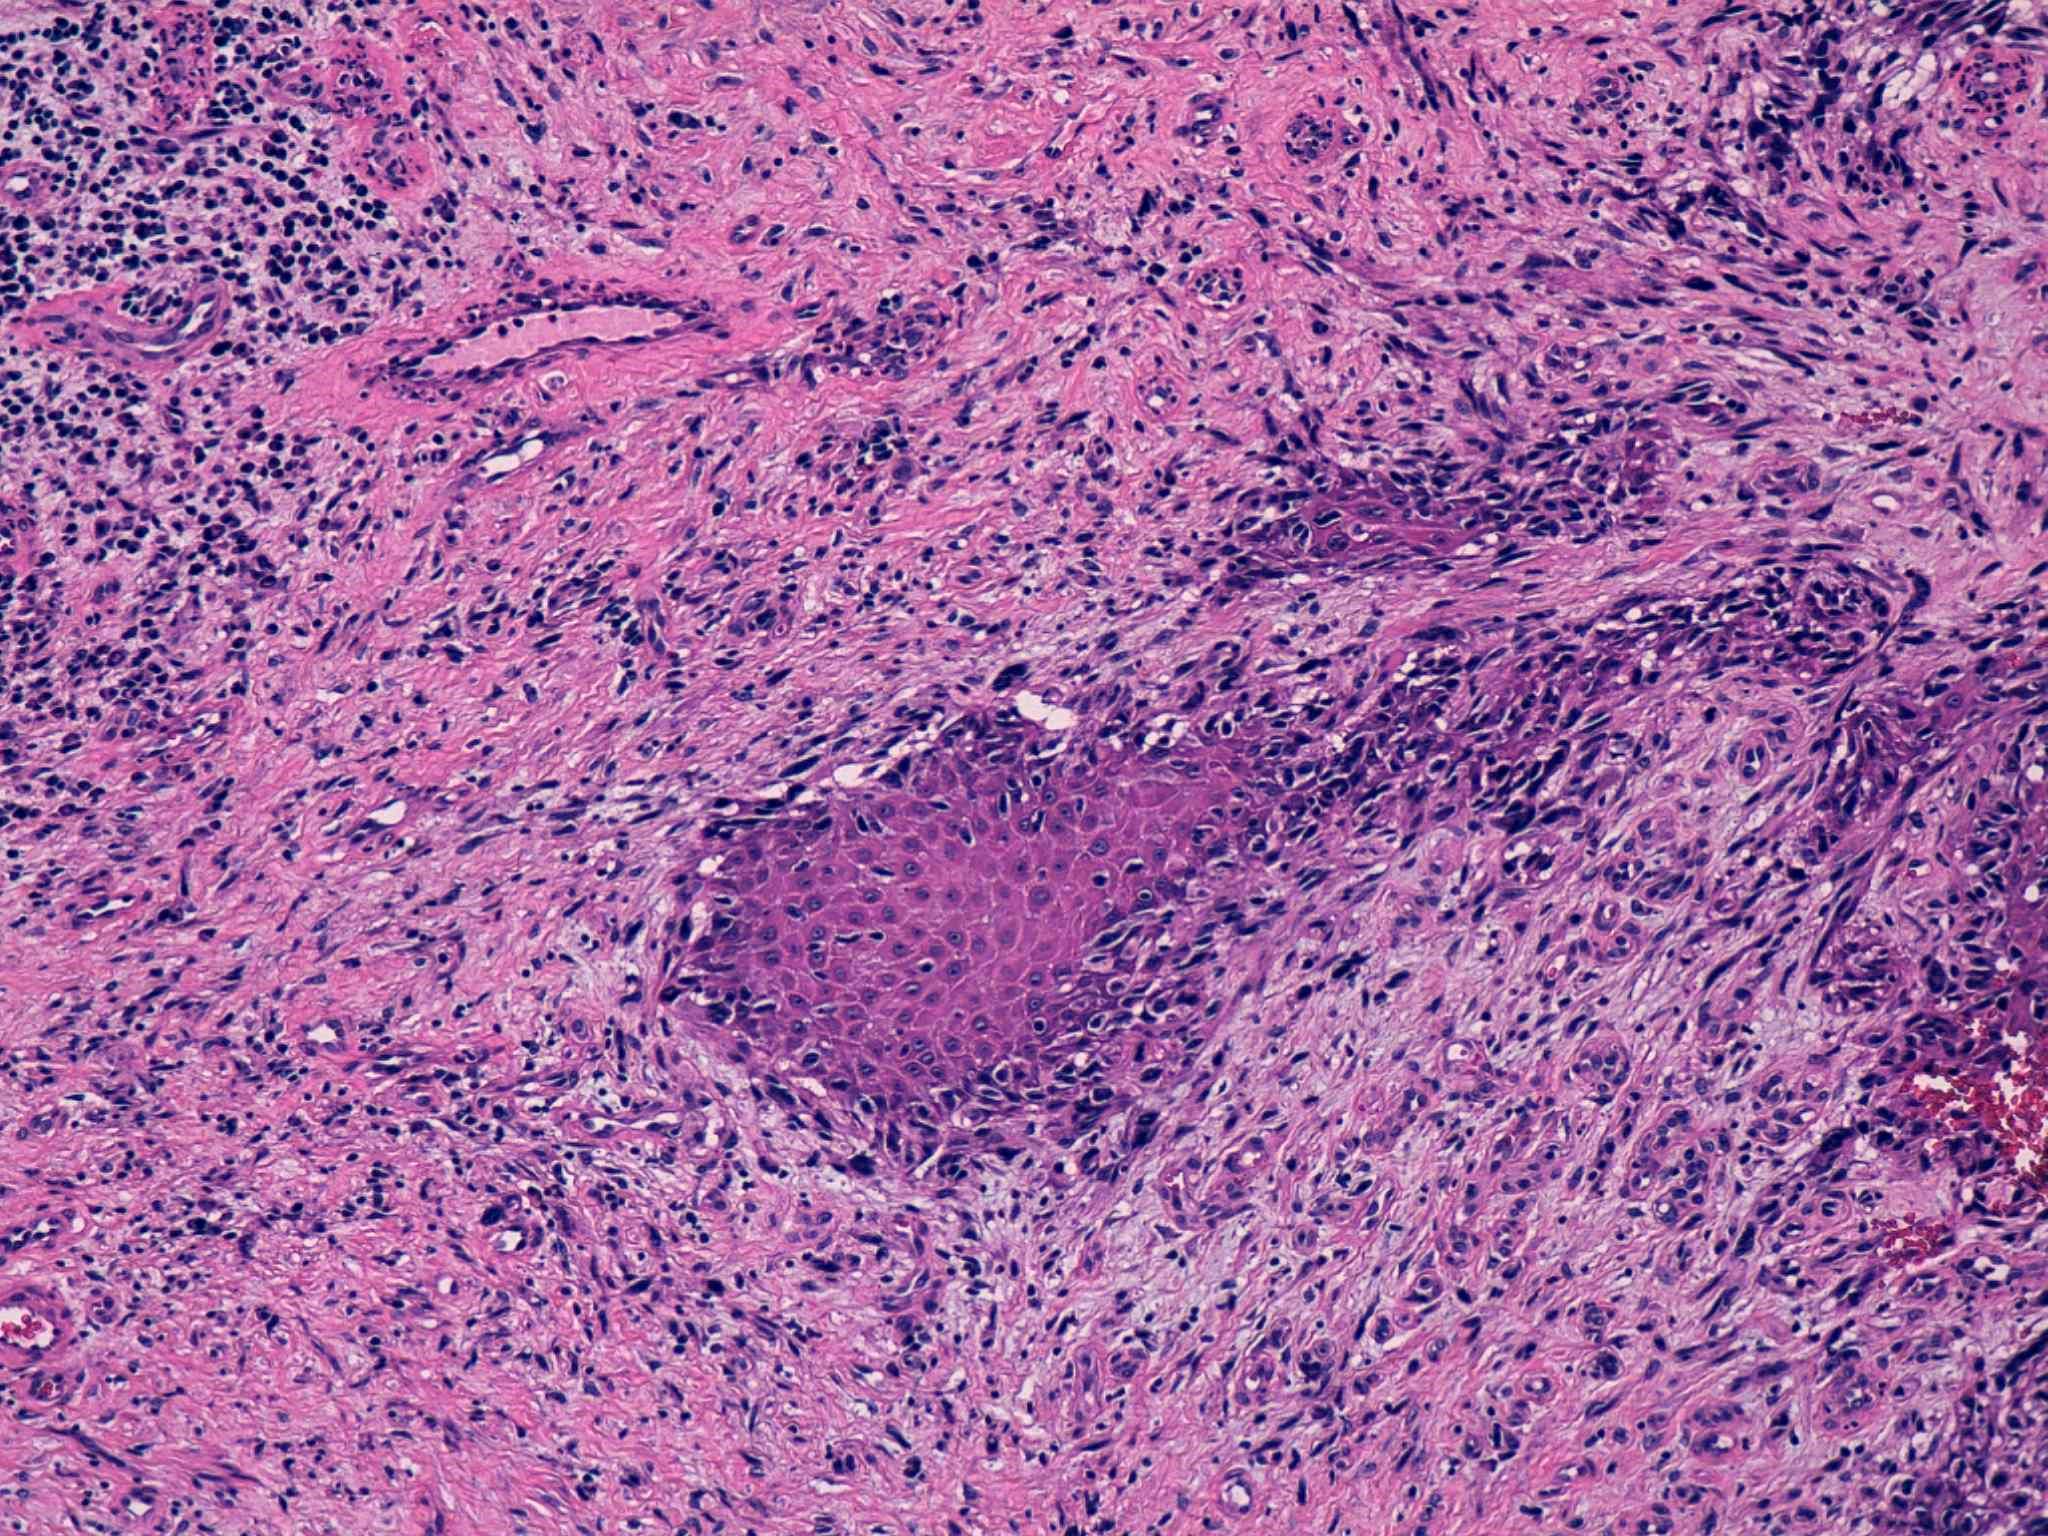

48 -- image_2011y10m04d_16h41m18s.jpg